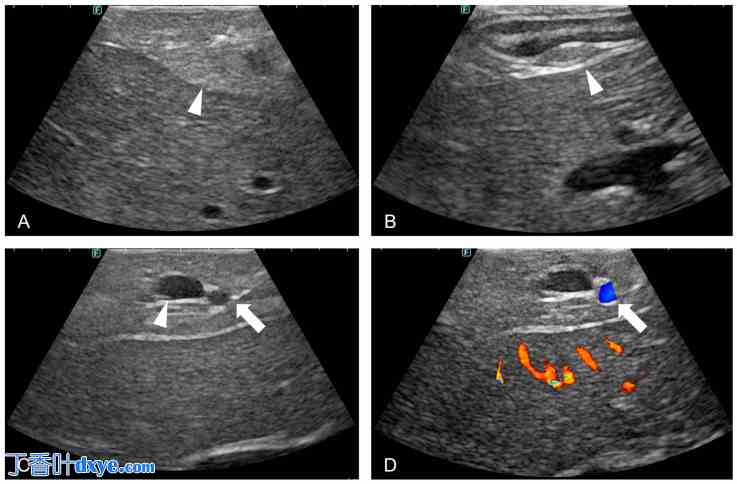

图 3.

犬胰腺及相关结构的超声成像。(A) 超声图像显示胰腺实质的回声纹理(箭头)。(B) 超声显示十二指肠大乳头(箭头)。 (C)超声图像显示胰十二指肠颅脑动脉和静脉(箭头)。(D)多普勒超声图像确认胰十二指肠颅脑动脉的动脉搏动和血管血流(箭头)。